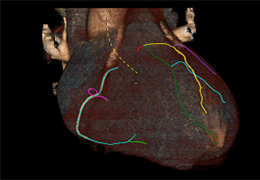

View X-Ray CT & MRI Scans Fast and Easily

Designed for surgeons, Pro Surgical 3D makes it easy to view patient scans quickly. Pro Surgical 3D facilitates the optimal 3D treatment and assessment workflows based on X-ray CT and MRI scans – and best of all, it’s FREE!

Everyone – including surgeons, patients and their loved ones – benefits from being better informed by the wealth of information buried within CT and MRI scans. Pro Surgical 3D gives surgeons more information to develop optimal treatment plans for patients. It also helps patients and their support group better understand their medical condition and proposed treatment options.

High-quality and fast 3D reconstruction and 3D rendering

Performs 3D reconstruction and volume rendering.

Side-by-side comparative assessment for pre- and post-operative scans.